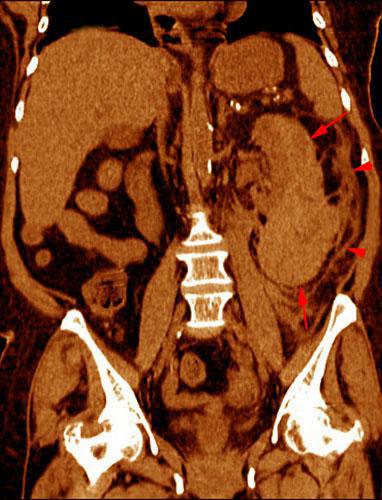

Hematoma subcapsular y perirrenal